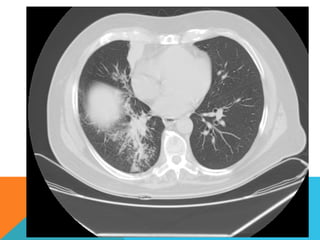

ABORDAJE TÉCNICO: Serealiza estudio con ventana mediastinal y de parénquima pulmonar con técnica de ALTA RESOLUCION, en inspiración y espiración, mediante  cortes axiales, desde ápices hasta bases pulmonares, con las siguientes observaciones En las partes blandas y las estructuras óseas dentro de los límites de la normalidad. Las regiones axilares libres. Ambos pulmones con neumatización conservada, con sobredistensión pulmonar, y áreas de atrapamiento aéreo, bilateral con cambios fibrosos cicatriciales apicales derechos. Se demuestran áreas de condensación en topografía predominantemente parenquimatosa pulmonar derecha, la mayor de ellas evidenciada hacia la base, acompañada de broncograma aéreo, la medición máxima al corte axial de 6.1 por 2.2 cm, en topografía del segmento posterior del lóbulo inferior, S10 así como también otra más se definen topografía de similares características en topografía del segmento medial del lóbulo medio, S5. En topografía parenquimatosa pulmonar izquierda imagen de similares características a las ya descritas en topografía del segmento lingular inferior, S4. No hay derrame ni áreas de engrosamiento pleurales. El patrón vascular es de características normales donde no se delimitan imágenes de lesiones aneurismáticas únicamente cambios por aortoesclerosis incipiente. El corazón de dimensiones conservada, de contornos regulares, sin desplazamientos; en la región hiliar derecha se define adenopatía de medición máxima corte axial de 1.6 por 1.4 cm.

En los cortesrealizados hacia las bases pulmonares es posible delimitar los órganos sólidos intraabdominales tales como el hígado sin anormalidades que consignar; se demuestra imagen hiperdensa puntiforme en topografía del parénquima esplénico en relación a calcificación inespecífica. Hay distensión aérea esofágica que lo define prácticamente su totalidad. Se demuestran imágenes hiperdensas en topografía intraluminal vesicular que corresponden con colelitiasis. Se define imagen hipodensa parenquimatosa renal superior derecha con patrón de atenuación homogéneo, líquido que condiciona la sospecha de lesión focal benigna tipo quística simple. INTERPRETACIÓN DIAGNÓSTICA:   ESTUDIO ANORMAL QUE DEMUESTRA HALLAZGO INESPECIFICO DE SOBREDISTENSIÓN PULMONAR  CON CAMBIOS FIBROSOS CICATRICIALES APICALES DERECHOS Y ÁREAS DE CONDENSACIÓN PARENQUIMATOSAS PULMONARES, DE PREDOMINIO DERECHO, LA DE MAYORES DIMENSIONES BASAL DERECHA, ASOCIADA CON BRONCOGRAMA AÉREO. COLELITIASIS.

El estudio radiológicosimple evidencia una lesión nodular menor del centímetro, radiodensa, caracterizada como granuloma cálcico. En mi opinión el estudio de TCAR fue realizado por ese motivo y ello permito identificar los hallazgos “floridos” que ya se señalan y se muestran en las imagen axiales ya seleccionadas.